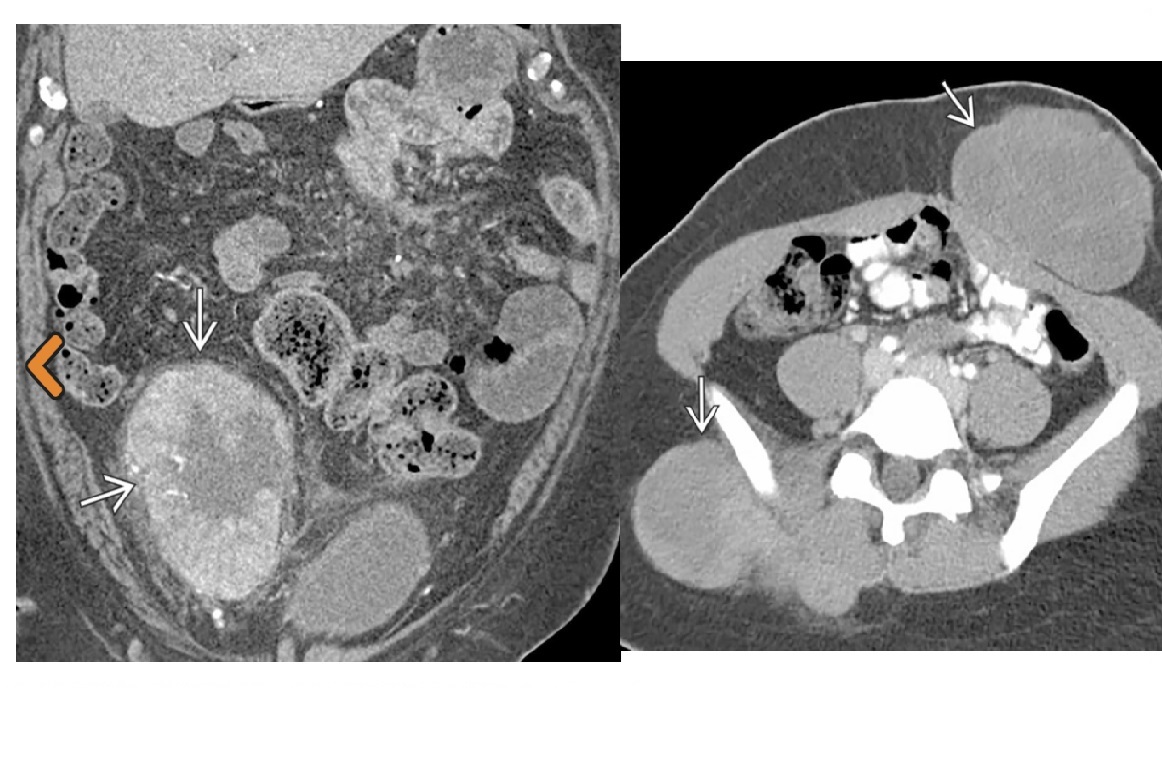

Carcinoid

spiculated mesenteric mass with calcification/ desmoplastic reaction

Tethering of SB loops

90% arise in terminal ileum/appendix

Hyper-vascular liver mets - Carcinoid syndrome

111I- Octreotide scans (1st - highest sensitivity)

or 123I-MIBG (for 10% dont take up octreotide)

for Dx and staging

Big centres use gallium PET

Assocaited with MEN 1 or MEN 2a

DDX

Sclerosing mesenteritis/ mesenteric pannicultuis

- FAT HALO sign - Mass envelop vessels, but preservation of fat around vessels

- usually jejunal small bowel mesentery